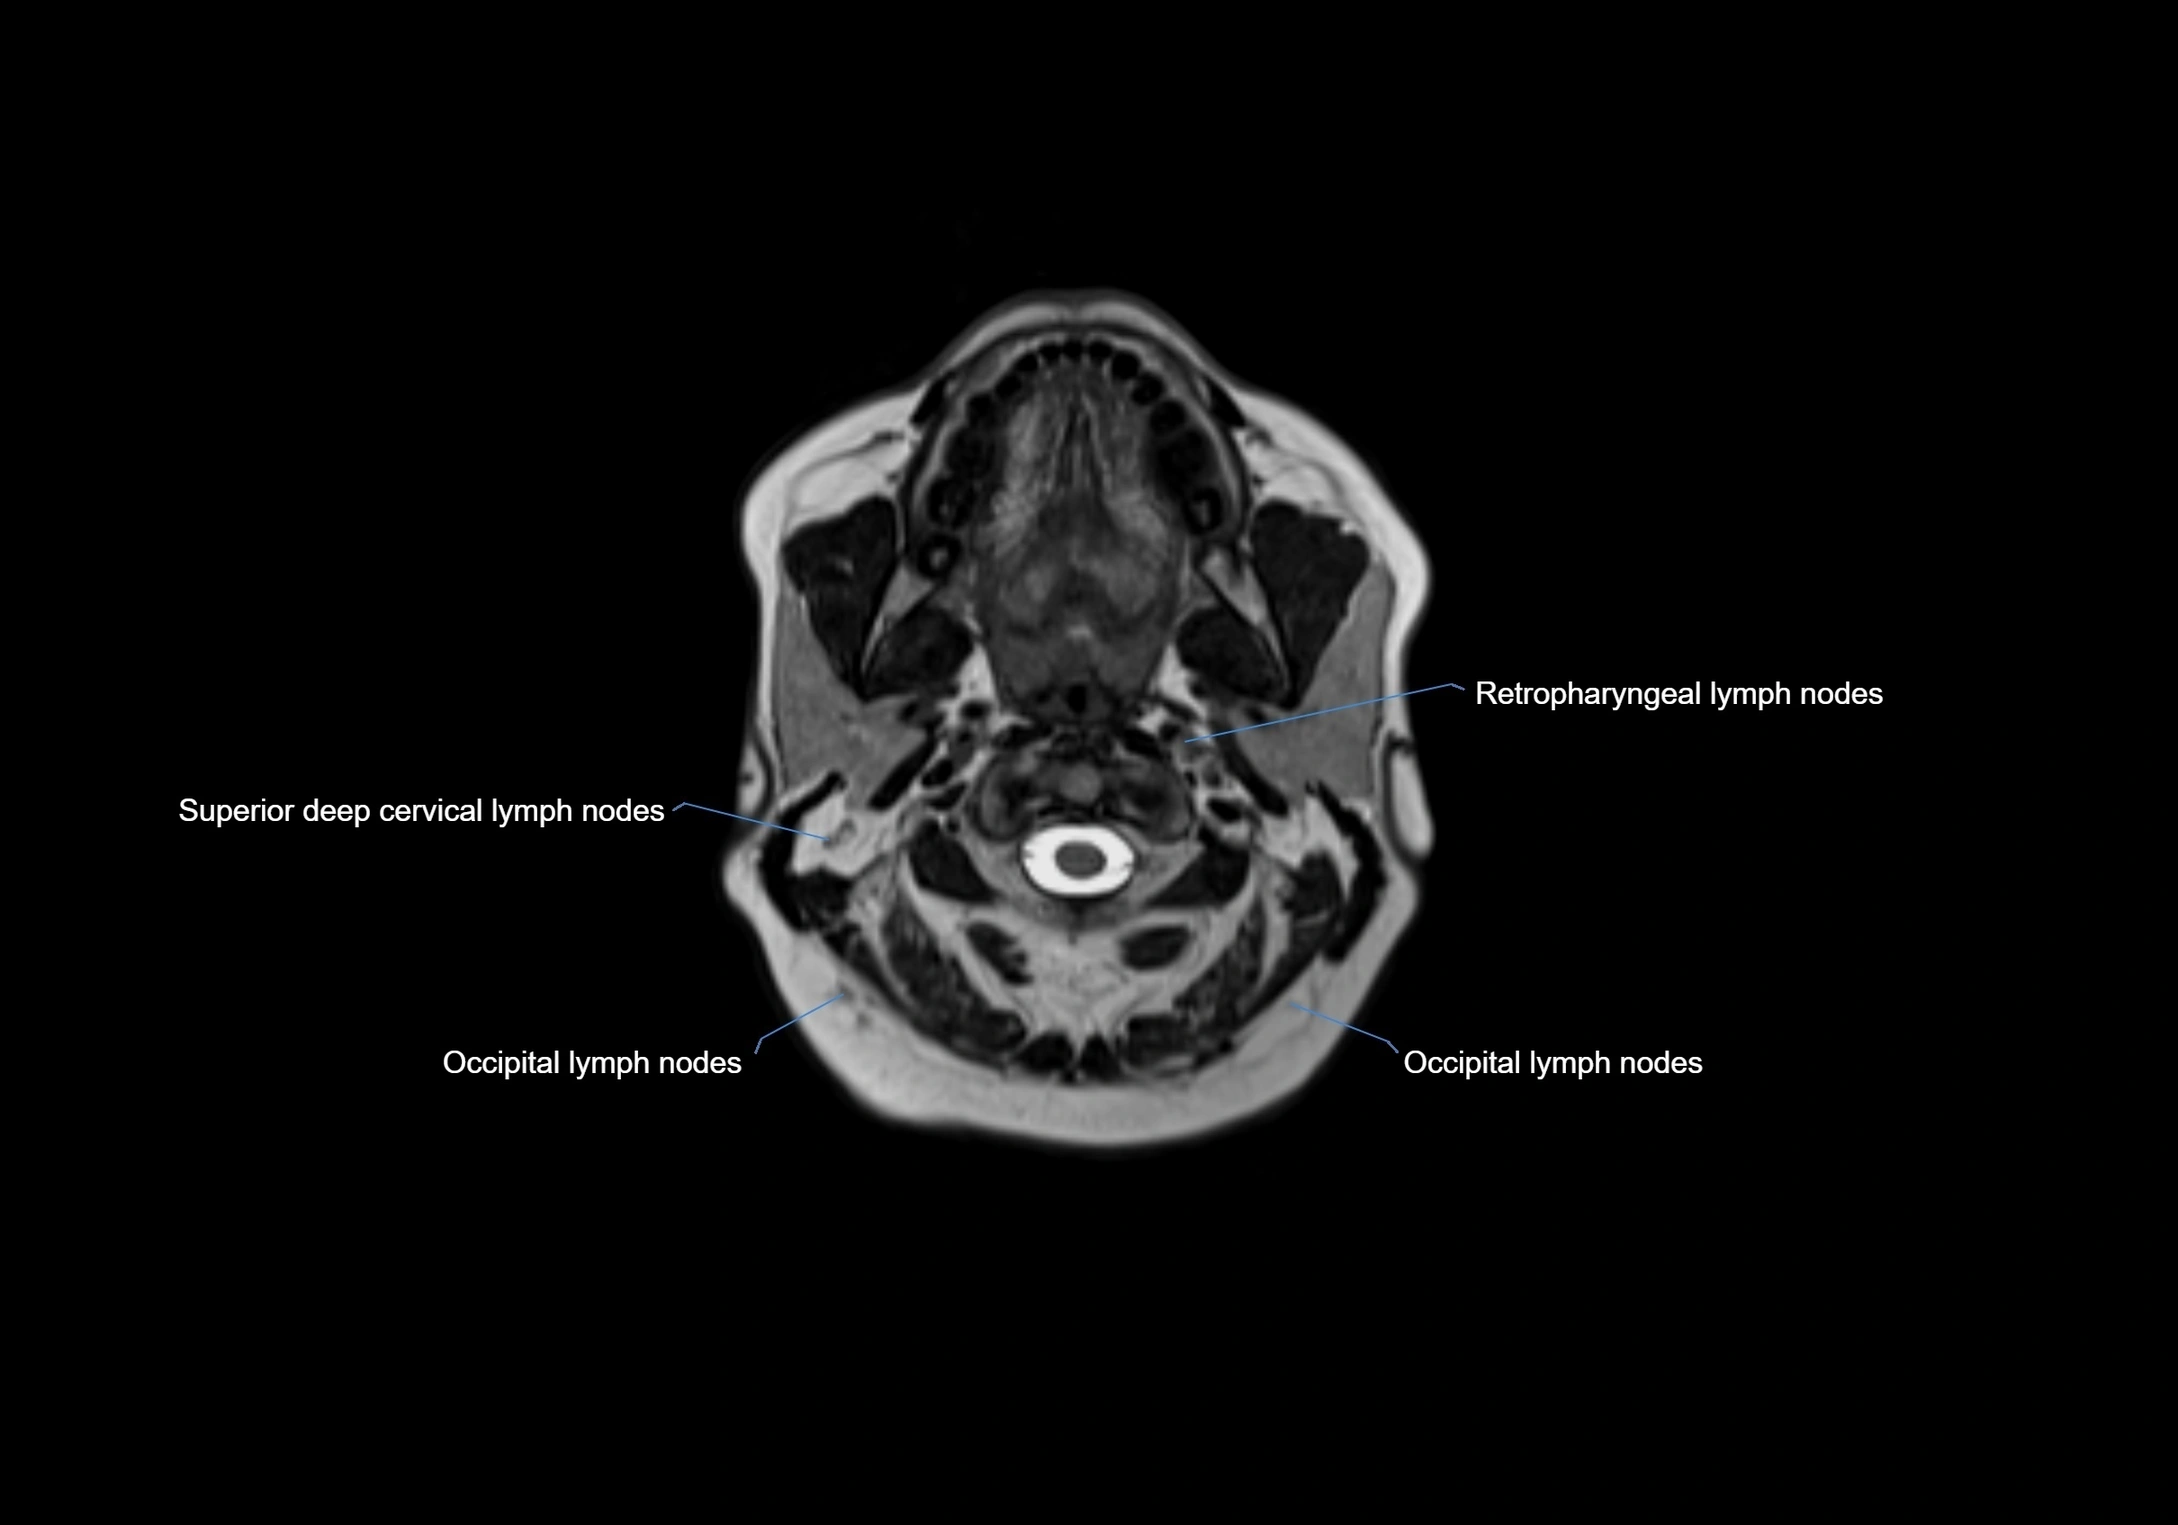

Location

• Found along primary lymph node chains, including preauricular, submandibular, parotid, and occipital regions

• Embedded in subcutaneous fat or superficial fascia, often lateral or posterior to primary nodes

MRI Appearance

T1-weighted images:

• Normal accessory nodes appear as small, oval hypointense to intermediate signal structures within subcutaneous fat

• Surrounded by hyperintense fat, enhancing contrast for visualization

• Pathological nodes may appear enlarged or rounded, sometimes with cortical thickening

MRI images

image